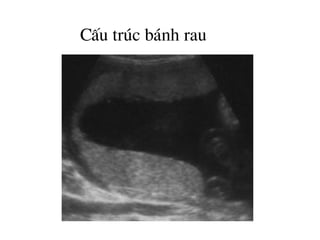

CÊu tróc b¸nh rau

H×nh ¶nh cÊu tróc b¸nh rau